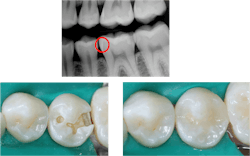

Cariostatic cements. Because of the scanner inaccuracies, milling devices, the ceramic pressing concept, and other issues, the margins of zirconia and lithium disilicate crowns are significantly more open than the metal restorations of the past. Resin-modified glass ionomer (RMGI) and conventional glass ionomer (GI) cements are cariostatic, but resin cements are composite and have the same characteristics as described previously for composite. Do we want these open margins and shrinking cements to cause caries on margins in a few years?

Historically, with a few exceptions, crowns did not come off in service. Zinc phosphate and conventional GI cements are rigid and strong and held the crowns on the tooth preparations. Resin cements are flexible and strong (figure 3). But one of the major reasons almost every dentist has had zirconia crowns coming off is the flexibility of resin cements and, to a lesser degree, the flexibility of the RMGI cements (figure 4).